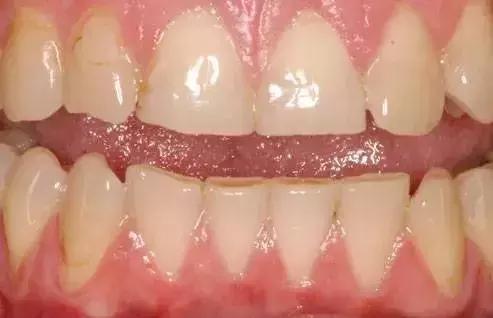

一些全身健康问题也会影响牙釉质。这张图中显示了暴食症患者的牙齿,由于常常呕吐,胃酸反流入口腔导致牙釉质被侵蚀。另外,胃食管返流综合症也会引起牙釉质的损坏。

这张图上能看到上下前牙都被磨低了。